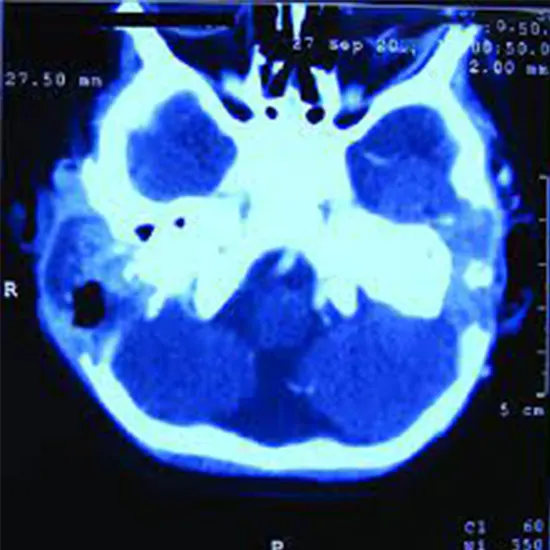

CECT Temporal bone Axial & Coronal is Contrast Enhanced Computed Tomography of Temporal bone axial & coronal view. The scan focuses on the lower part of the skull and its surrounding soft tissues.  The doctor recommends this scan to diagnose the conditions related to hearing loss, chronic ear infections, and middle and inner ear diseases. In this scan contrast media is used to identify the defects/ disorders.

Why is CECT Temporal Bone Axial and Coronal?

• To detect/diagnose the temporal bone tumour which causes problems in the inner and middle ear.

• To diagnose conditions such as hearing loss, chronic ear infections, and middle and inner ear diseases

• To detect/diagnose injuries to the facial nerve, middle and inner ear, facial nerve paralysis, haemorrhage, brain injury etc.